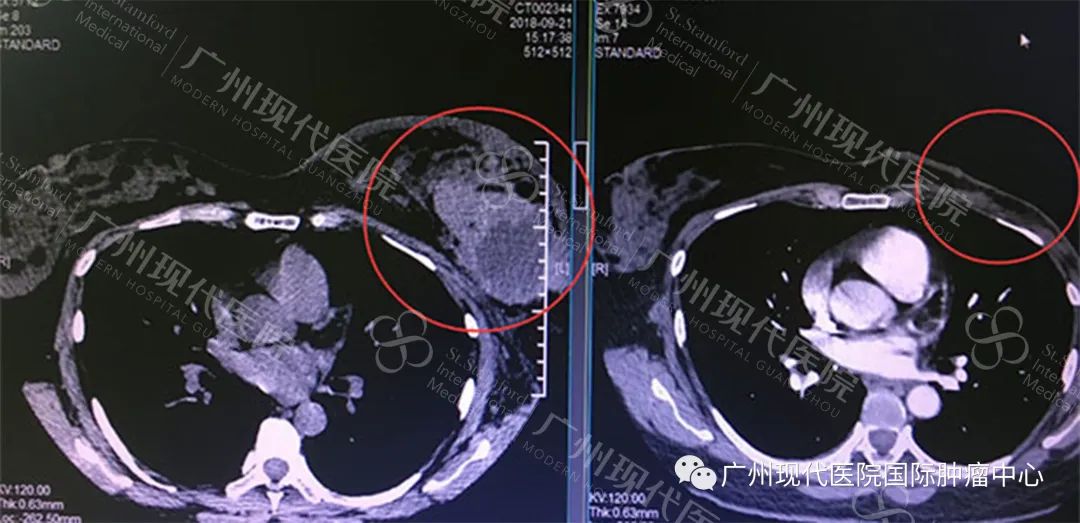

據(jù)趙醫(yī)生介紹,經(jīng)過一系列的介入、冷凍治療配合放療,曬噠的腫塊慢慢變小,左乳房的疼痛也逐步減輕,2019年復(fù)查時(shí),顯示左乳房約12*7.5cm大小的腫塊消失了,曬噠的抗癌取得了初步的勝利。

左:2018年9月腫瘤影像,右:2019年6月影像